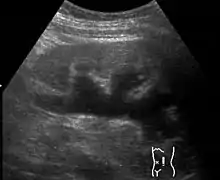

Actuellement la plupart de ces dilatations pyélocalicielles sont mises en évidence lors des échographies fœtales. Chez l'enfant plus grand le syndrome de jonction peut être diagnostiqué à l'occasion de douleurs abdominales ou d'une hématurie, souvent à la suite d’un traumatisme mineur. L'infection urinaire est rare dans cette pathologie.

Les examens les plus communément utilisés pour détecter ce syndrome sont l'urographie intraveineuse, l'uroscanner, l'échographie des voies urinaires et la scintigraphie rénale au DTPA (diethylene triamine pentaacetic acid en anglais, « acide diéthylène triamine penta acétique » en français).